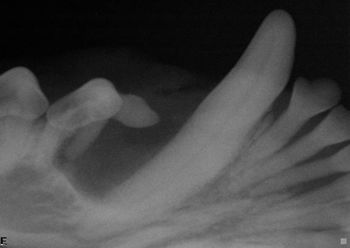

The tooth-seeking adventure continues with Mary Berg and the deceptive dental radiograph discovery.

You have to have a solid understanding of the basicsand whats normalbefore you can leap to abnormal, says Dr. Barden Greenfield.

The cat, which had history of heartworm disease, presented with rear leg lameness.